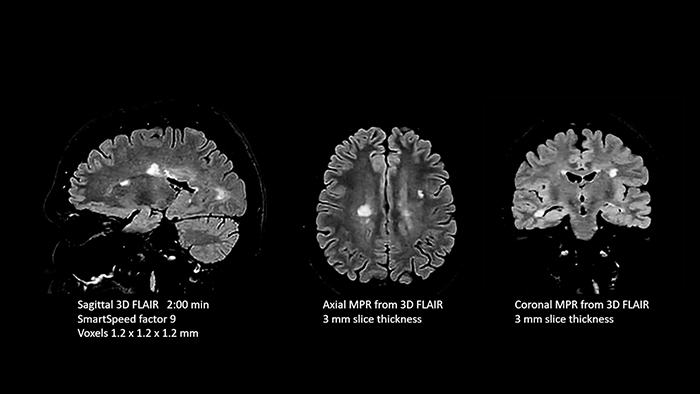

In this examination SmartSpeed is used to reduce scan times. All three FLAIR orientations were obtained with only one 3D sequence using SmartSpeed. Performed with 1.5T Ambition X, dS Head coil.